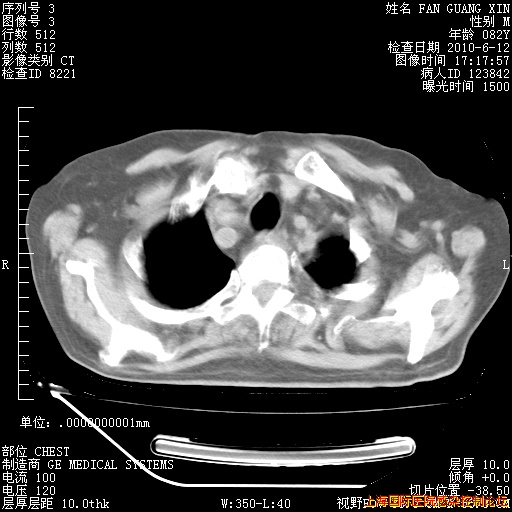

6月12日纵膈窗

整整相隔30天的肺部CT好像有所好转啊。甲强龙减量第3天,需要观察体温。

海管,自昨日你和我通完话后,不知您岳父消化道症状有无缓解?体温怎样?阅读7.12日胸部ct,个人认为目前激素治疗是有效的,甲强龙减量是适宜的。因在抗痨治疗,需密切观察肝功、肾功能和血常规。不过,老年、长期住院和大量使用激素,很担心菌群失调发生